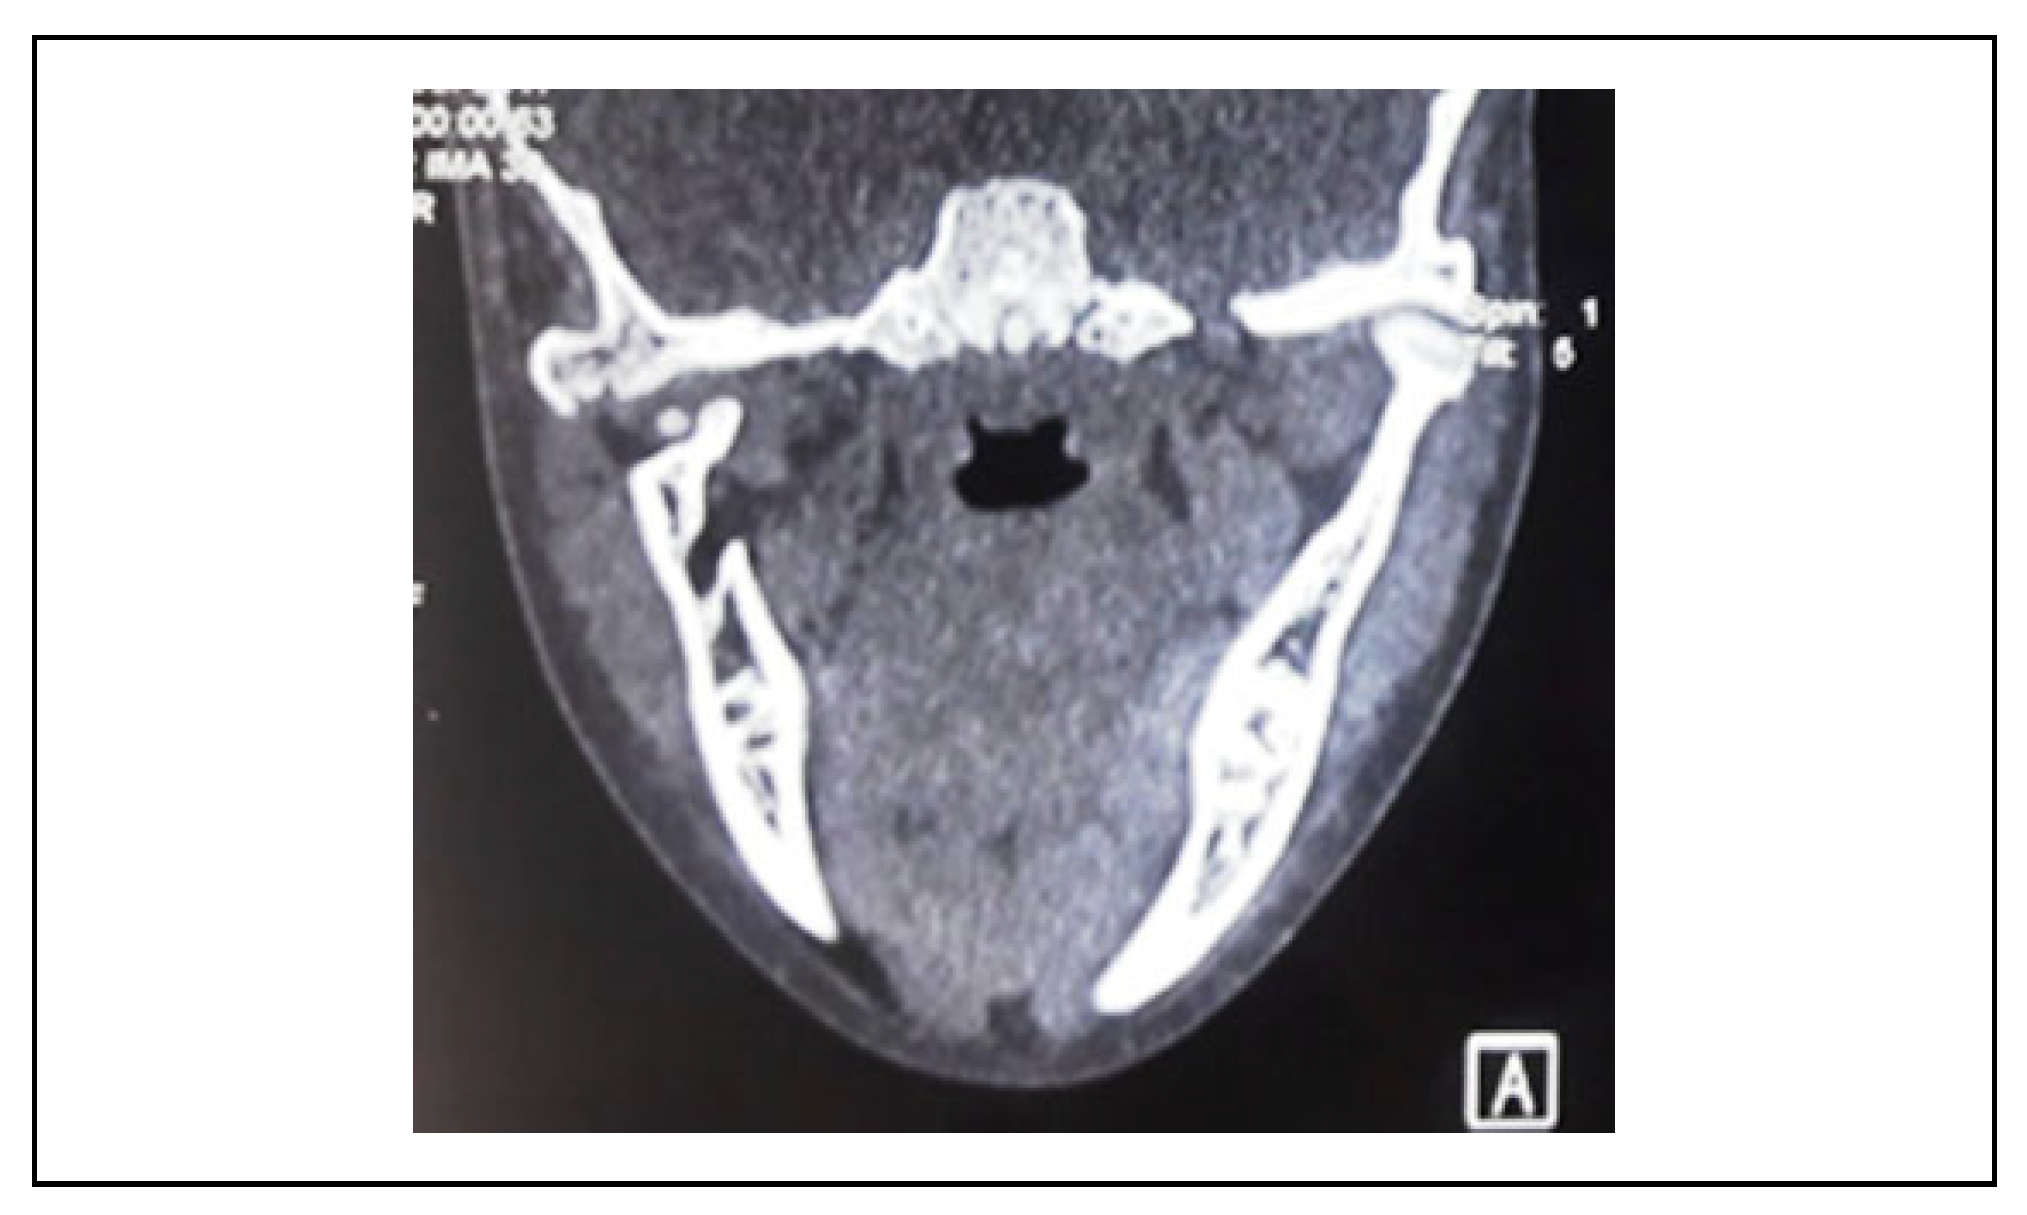

A Clinical and Radiological Investigation of the Use of Dermal Fat Graft as an Interpositional Material in Temporomandibular Joint Ankylosis Surgery

Rahman, S.A.; Rahman, T.; Hashmi, G.S.; Ahmed, S.S.; Ansari, M.K.; Sami, A. A Clinical and Radiological Investigation of the Use of Dermal Fat Graft as an Interpositional Material in Temporomandibular Joint Ankylosis Surgery. Craniomaxillofac. Trauma Reconstr. 2020, 13, 53-58. https://doi.org/10.1177/1943387520903876